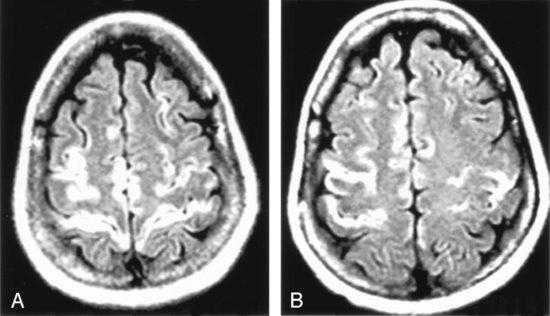

Т1-взвешенное корональное изображение после введения контраста демонстрирует асимметричное двустороннее гириформное и лептоменингальное контрастное усиление больше в области коры островка (большие стрелки) и поясной извилины (меньшая стрелка)